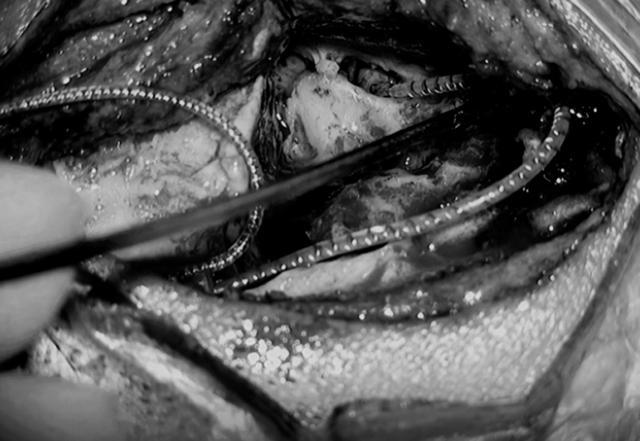

▲术中耳蜗植入